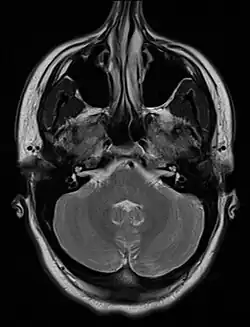

Skrzywienie przegrody nosowej (łac. deviatio septi nasi) – wrodzona lub nabyta deformacja przegrody nosowej.

Nabyte skrzywienie przegrody nosowej powstaje najczęściej na skutek przebytego urazu nosa w większości przypadków współistniejącego ze złamaniem kości nosowych.

Zgodnie z teorią opracowaną przez Vernona D. Graya, wrodzone skrzywienie przegrody nosowej powstaje na skutek nieprawidłowego ułożenia płodu w macicy i urazów okołoporodowych. W swojej pracy Gray wykazał częstsze występowanie skrzywienia przegrody nosowej u dzieci pierworódek oraz w przypadkach, w których drugi okres porodu trwał ponad 15 minut. Odnotował również zależność między kierunkiem skrzywienia przegrody nosowej a kierunkiem IV zwrotu płodu[1].

Opisana przez Graya hipotetyczna linia, tzw. linia Graya, łącząca kolec nosowy przedni z dziobem klinowym kości klinowej stanowi umowną granicę: do przodu i ku górze, od której większość deformacji przegrody nosowej ma przebieg pionowy, do dołu i ku tyłowi zaś − przebieg poziomy[2].